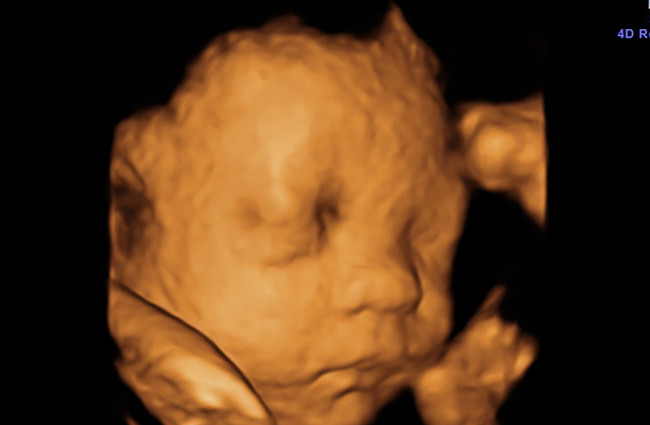

四维彩超采用新式的高清摄像仪,图像是立体的,更清晰,并能够多方位、多角度地观察宫内胎儿的生长发育情况,为早期诊断胎儿先天性体表畸形和先天性心脏疾病提供准确的科学依据。四维彩超不仅可以测定胎儿胎龄,还可以对胎儿的身体发育情况、心肺功能情况、是否有唇腭裂等进行准确的排查,而这些,是普通B超所做不到的。

四维彩超是拍摄的动态画面,为了看清宝宝的脸部,还需要对局部放大,就跟我们平时用手机拍照一样的道理。

宝宝在子宫内,外围又有羊水包围,自然而然的画面会有失真或重叠,有些局部会放大,如果拍的时候正处在局部放大的状况,那宝宝拍出来,自然好看不到哪去。另外,怀孕6个月时宝宝身体上有胎脂,凹凸不平的,也会影响到成片效果。

我家宝宝做四维彩超的时候,拍出来也是很丑,就像外星人一样,一看周围那些出来结果的宝宝也是同样的情况就放心了很多。